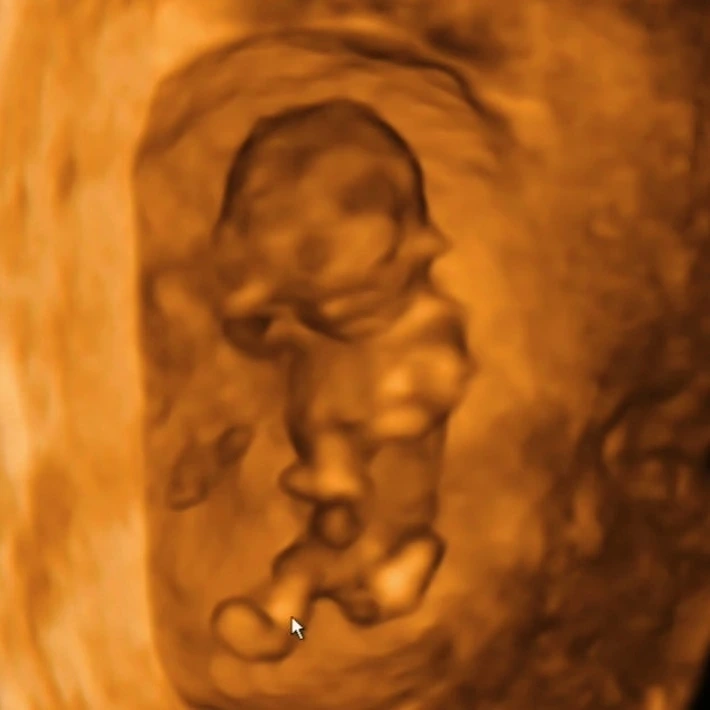

제법 많이 큰 우리 호랭이 (11주 4일차 입체초음파)